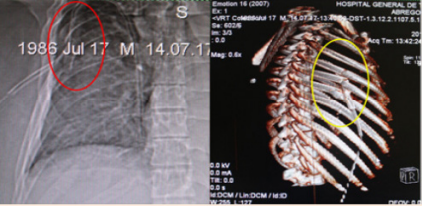

Rib fractures: Rib fractures are the most common injuries in trauma centers and secondary care hospitals. They are commonly seen in adults, usually secondary to blunt trauma that can be an insignificant injury or rather can lead to serious complications due to injuries of the internal organs. Rib fractures are clinically manifested bylocaltenderness, hematomas, inspiratory pain or while coughing. They tend to be complicated with pneumonia, flail thorax, hemothorax, hemopneumothorax, pulmonary contusions, or vascular lesions. It is mandatory to initiate an effective analgesic plan, being the most proper regional techniques. Byun and Kim9 studied retrospectively 327 patients with an average of 4.8 rib fractures finding flail chest in 22.3%, pulmonary contusion 22%, pneumothorax 31%, hemopneumothorax 20%, hemothorax 62%. 4.3% where complicated with pneumonia and 95% of all the patients were treated with antibiotics. The mortality rate was 5.3%. Studies have shown that patients with multiple rib fractures have a decreased quality of life after three years of the initial injury. Only 71% returns to their regular work10 (Figure 1).

Figure 1 1 Rib fractures, pneumothorax and lung contusion.